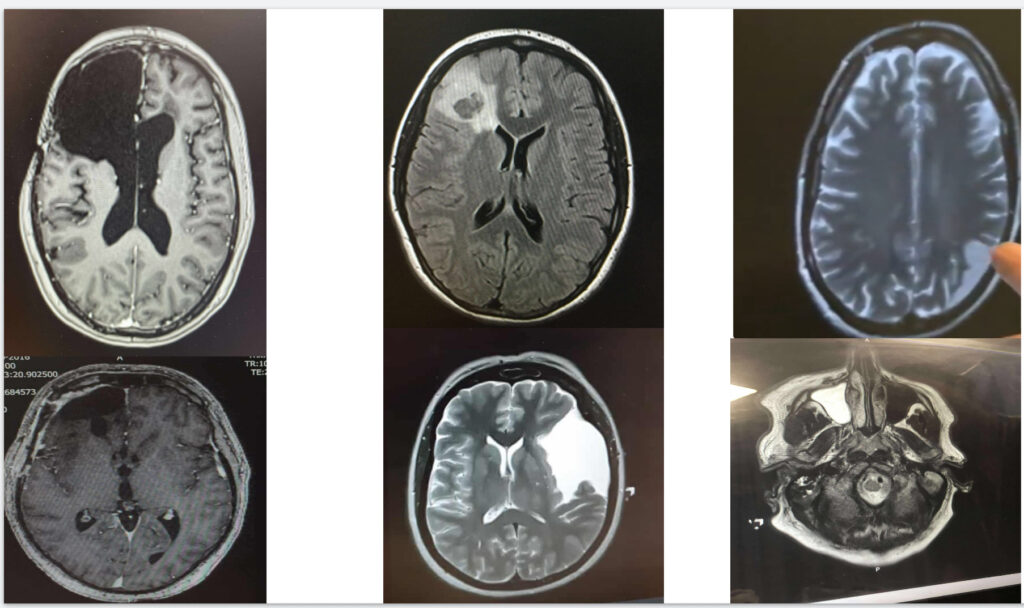

Angie Seaway creates the powerful works using real medical images sent to her by patients.

The scans come from people who have suffered strokes, aneurysms and other serious medical events.

With their consent, Angie turns the black-and-white images into vivid works of art in a project that has become a heartfelt tribute to the NHS.

“A brain scan is just black and white.

“But by adding colour it revealed a kind of hidden beauty in them.